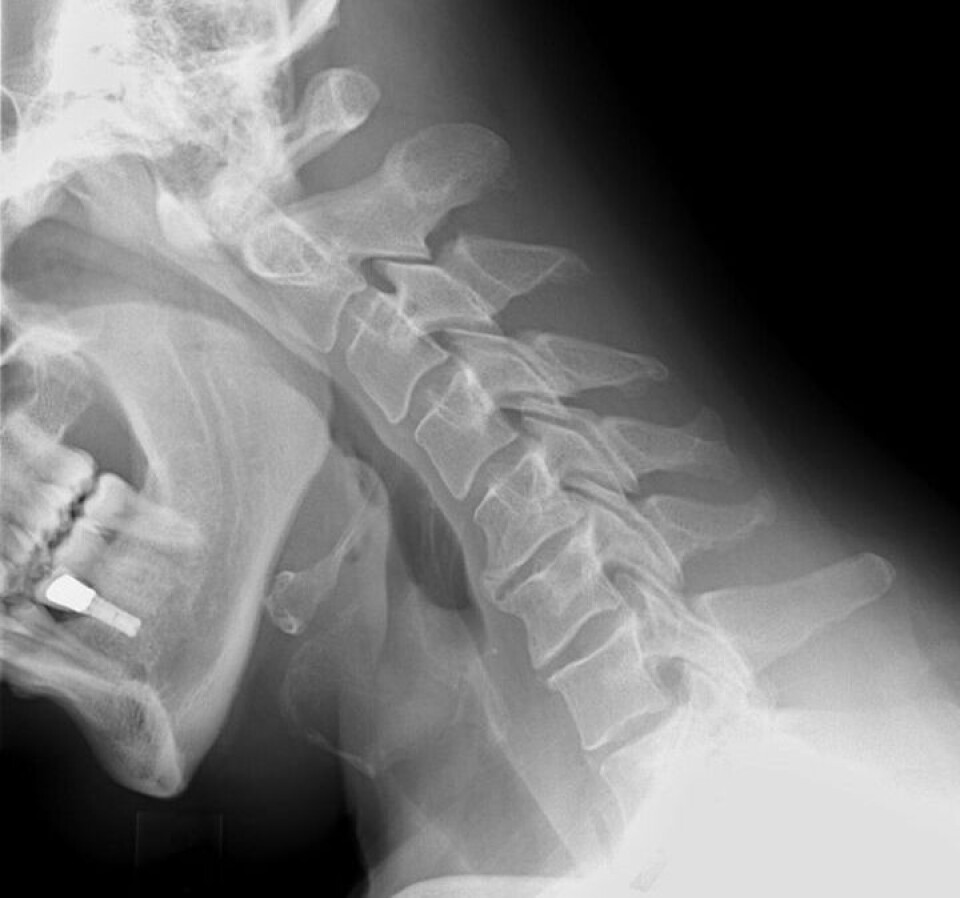

Illustrasjonsfoto: Røntgen nakke UTEN fraktur.